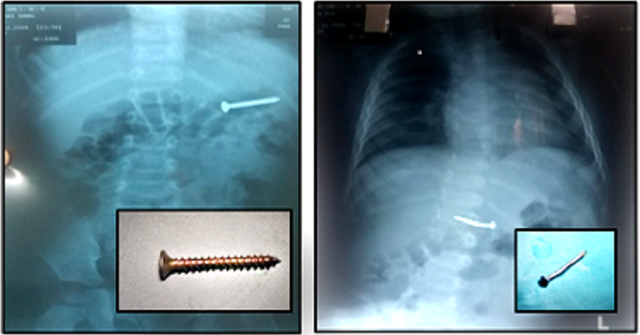

Dị vật là những chiếc đinh nằm trong đường tiêu hóa của trẻ

Trường hợp thứ 2 là bé trai N.T.Q. (15 tháng tuổi, ngụ tại quận Gò Vấp, TPHCM). Cháu nhập viện trong tình trạng mệt, đau bụng, bỏ ăn, quấy khóc. Sau khi khai thác bệnh sử không ghi nhận những dấu hiệu bất thường, bệnh nhi được bác sĩ kiểm tra hình ảnh thì phát hiện dị vật cản quang hình chiếc đinh nhọn trong đường tiêu hóa.